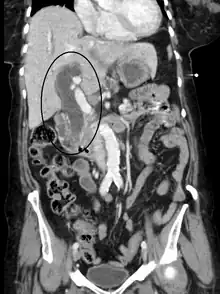

Posthepatic jaundice (obstructive jaundice) is caused by a blockage of bile ducts that transport bile containing conjugated bilirubin out of the liver for excretion.[30] This is a list of conditions that can cause posthepatic jaundice:

- Pancreatic cancer of the pancreatic head

Imaging

Medical imaging such as ultrasound, CT scan, and HIDA scan are useful for detecting bile-duct blockage.[41]